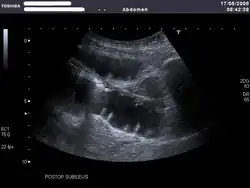

Bei Ileusverdacht liefert die Sonographie schnelle Hinweise: Man kann bei Vorliegen eines Ileus oft eine typische Pendelperistaltik sehen, d. h., der Darminhalt pendelt hin und her. Auch findet man verbreiterte, übermäßig mit Luft oder Flüssigkeit gefüllte Darmschlingen. Man kann oft den Ort des Verschlusses eingrenzen. Darmabschnitte hinter einem mechanischen Hindernis sind kollabiert (Hungerdarm).[5]